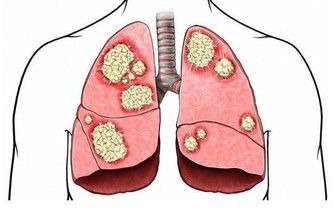

有研究表明,大多數長期口臭的人體內大腸桿菌和幽門螺桿菌的數量均比正常人多。其中幽門螺旋桿菌不僅會造成口臭,其還是造成胃癌的主要元兇。所以日常生活中應注意積極消滅胃腸道有害菌,保持胃腸道健康。